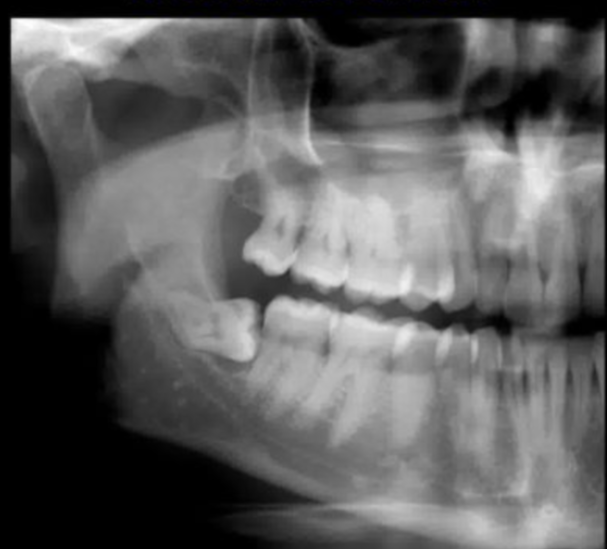

Q

when may we consider an OPG when assessing periapical inflamm pathology?

A

when periapical already taken and lesion not demonstrated v well, so we may want a larger view

or it may be a dose benefit for a pt with grossley decayed teeth